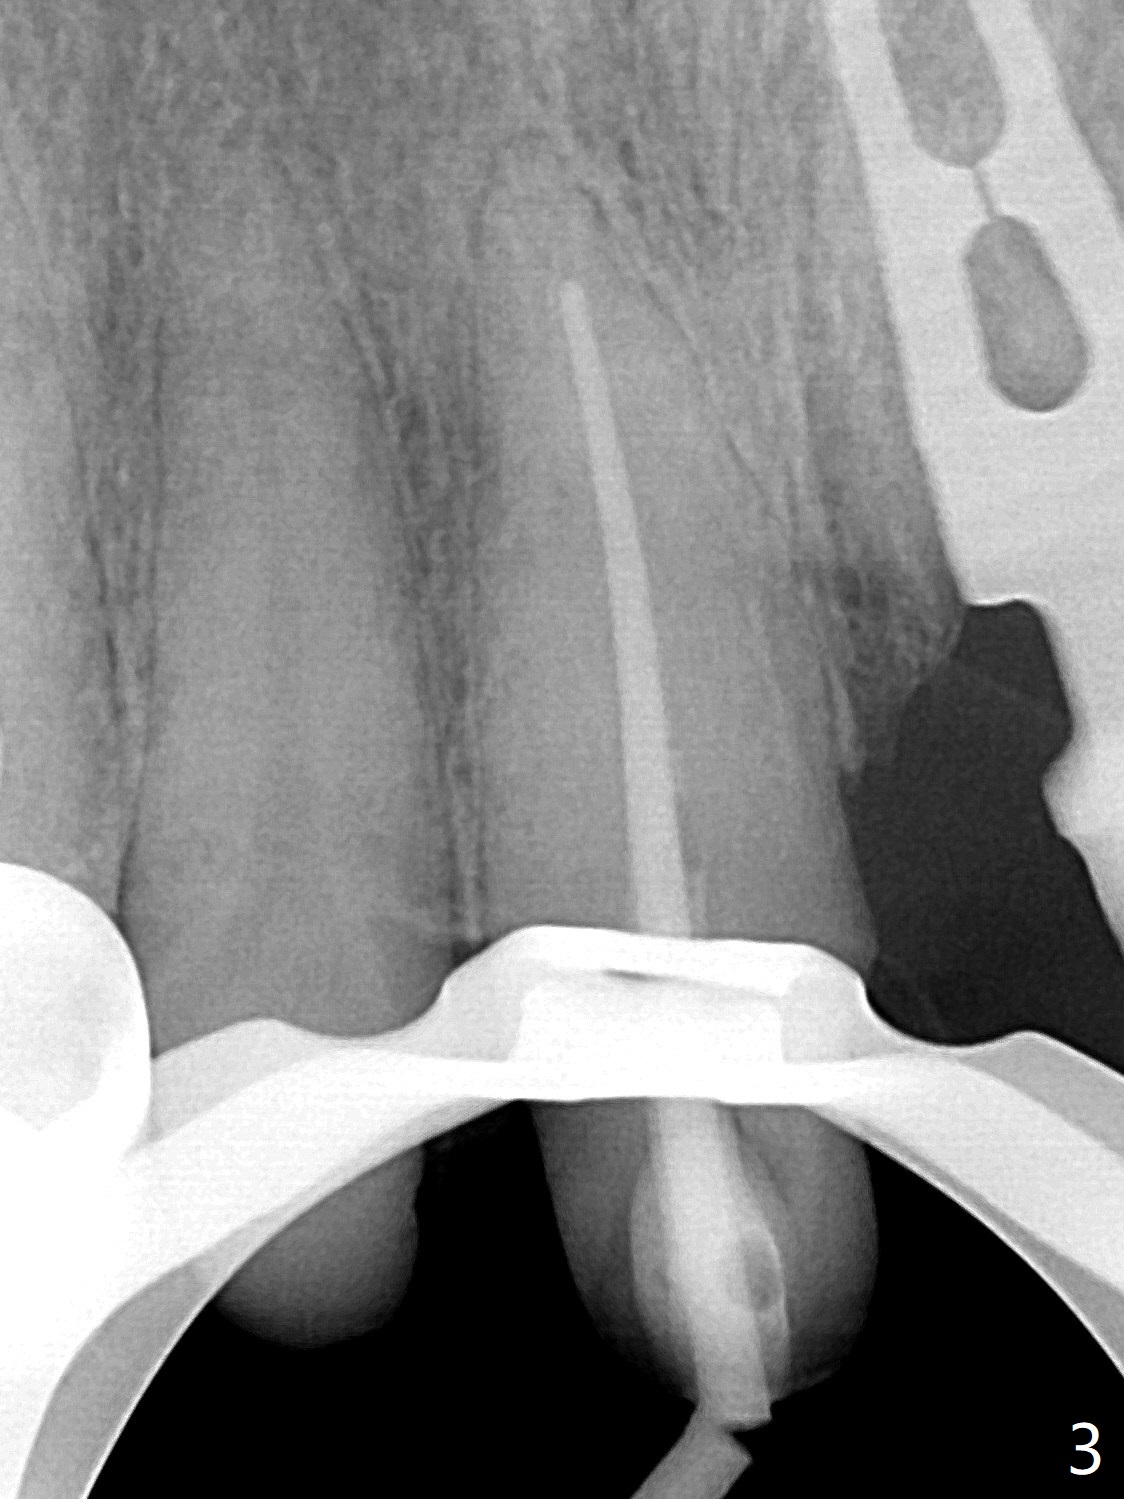

58岁女前牙桥撤除后三个月右上1(8号牙)出现牙髓炎,利用三个月前拍摄CT测定工作长度21.5毫米(图一),与术中根尖测定仪一致,但是40/.04 master cone没有达到工作长度(图二),再次使用根尖测定仪,工作长度22毫米,master cone空管临床上好像达到工作长度,但是加上糊剂,master cone临床上仍然不到工作长度,与根尖片一致(图三),三次切除牙胶尖,三次垂直压缩,仍然没有缓解长度问题(图四)。但愿临床上没有问题,此例是活髓。最终牙冠应用临时粘固剂。如果使用细的牙胶尖(考虑年龄因素),例如30/.04,可能简单些。